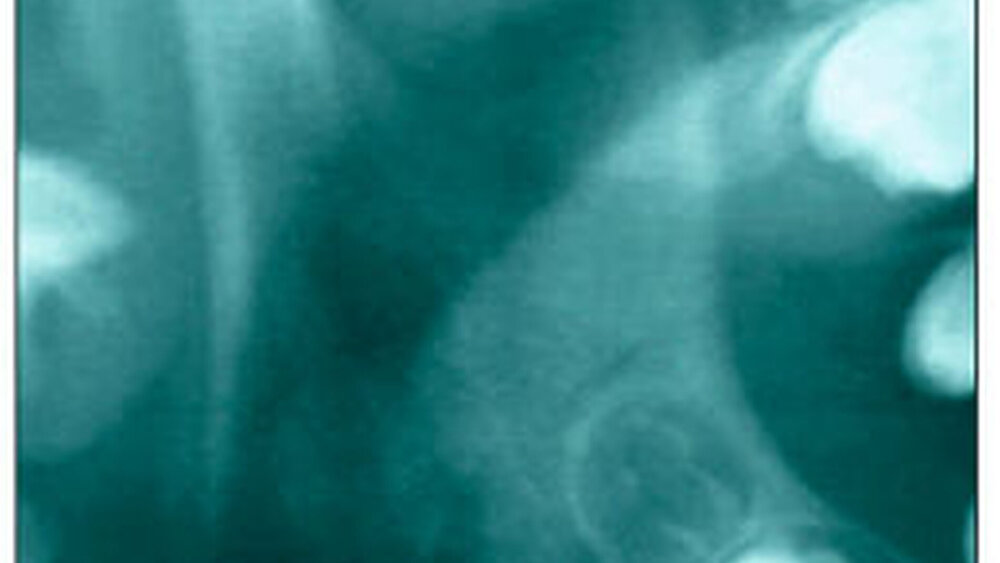

Bei 152 durchschnittlich 12-jährigen Rheumapatienten wurden die kondyläre Morphologie und Symmetrie beziehungsweise Asymmetrie im Vergleich zu einer Kontrollgruppe anhand der OPG analysiert. Zur Analyse erfolgte die Zuordnung zu vier morphologischen Graden je Kondylus (Abbildung 3a-d). Bei 45 Prozent der Rheumapatienten waren morphologische Veränderungen im Rahmen kondylärer Resorption unterschiedlicher Ausprägung zu finden. Die „Kontrollpatienten“ ohne JIA zeigten nur zu 14 Prozent formatypische Kondylen. Der Unterschied zwischen den beiden Gruppen war signifikant. Daher sollte bei der Routineauswertung von Panoramaröntgenschichtaufnahmen auf diese Anzeichen geachtet werden, insbesondere auch unter dem Aspekt, dass laut Assaf [2011] durchschnittlich 4,3 Jahre zwischen Erstmanifestation der JIA und Erstvorstellung in der Rheumasprechstunde des UKE liegen.

Zur hochauflösenden Sonografie (US) bestätigte ein Vergleich US vs. MRT [Assaf, 2011] anhand der oben genannten 20 Patienten in der Mehrzahl eine Übereinstimmung. Gemäß Jank et al. [Jank et al., 2005; Jank, 2007] sind Gelenkergüsse (durch hohe Entzündungsaktivität der JIA) sehr gut mittels hochauflösender US-Diagnostik darstellbar (Sensitivität 81 Prozent, Spezifität 100 Prozent, Genauigkeit 95 Prozent). Assaf et al. kamen zu dem Schluss, dass die Sensitivität der MRT höher ist als die der Sonografie, vor allem bei der Evaluierung akut entzündlicher Prozesse, jedoch die hochauflösende US-Diagnostik als Screening-Verfahren überaus interessant ist, um frühzeitig Veränderungen zeitnah und effektiv behandeln und ein Fortschreiten der Destruktion aufhalten zu können [Assaf, 2011; Assaf et al. 2013]. Assaf bezifferte für einen Kiefergelenkerguss bei JIA auf 100 Prozent Sensitivität, Spezifität und Genauigkeit, relativierte jedoch für entzündliche Veränderungen im Bereich des Discus articularis (Sensitivität 82 Prozent, Spezifität 87 Prozent, Genauigkeit 86 Prozent).